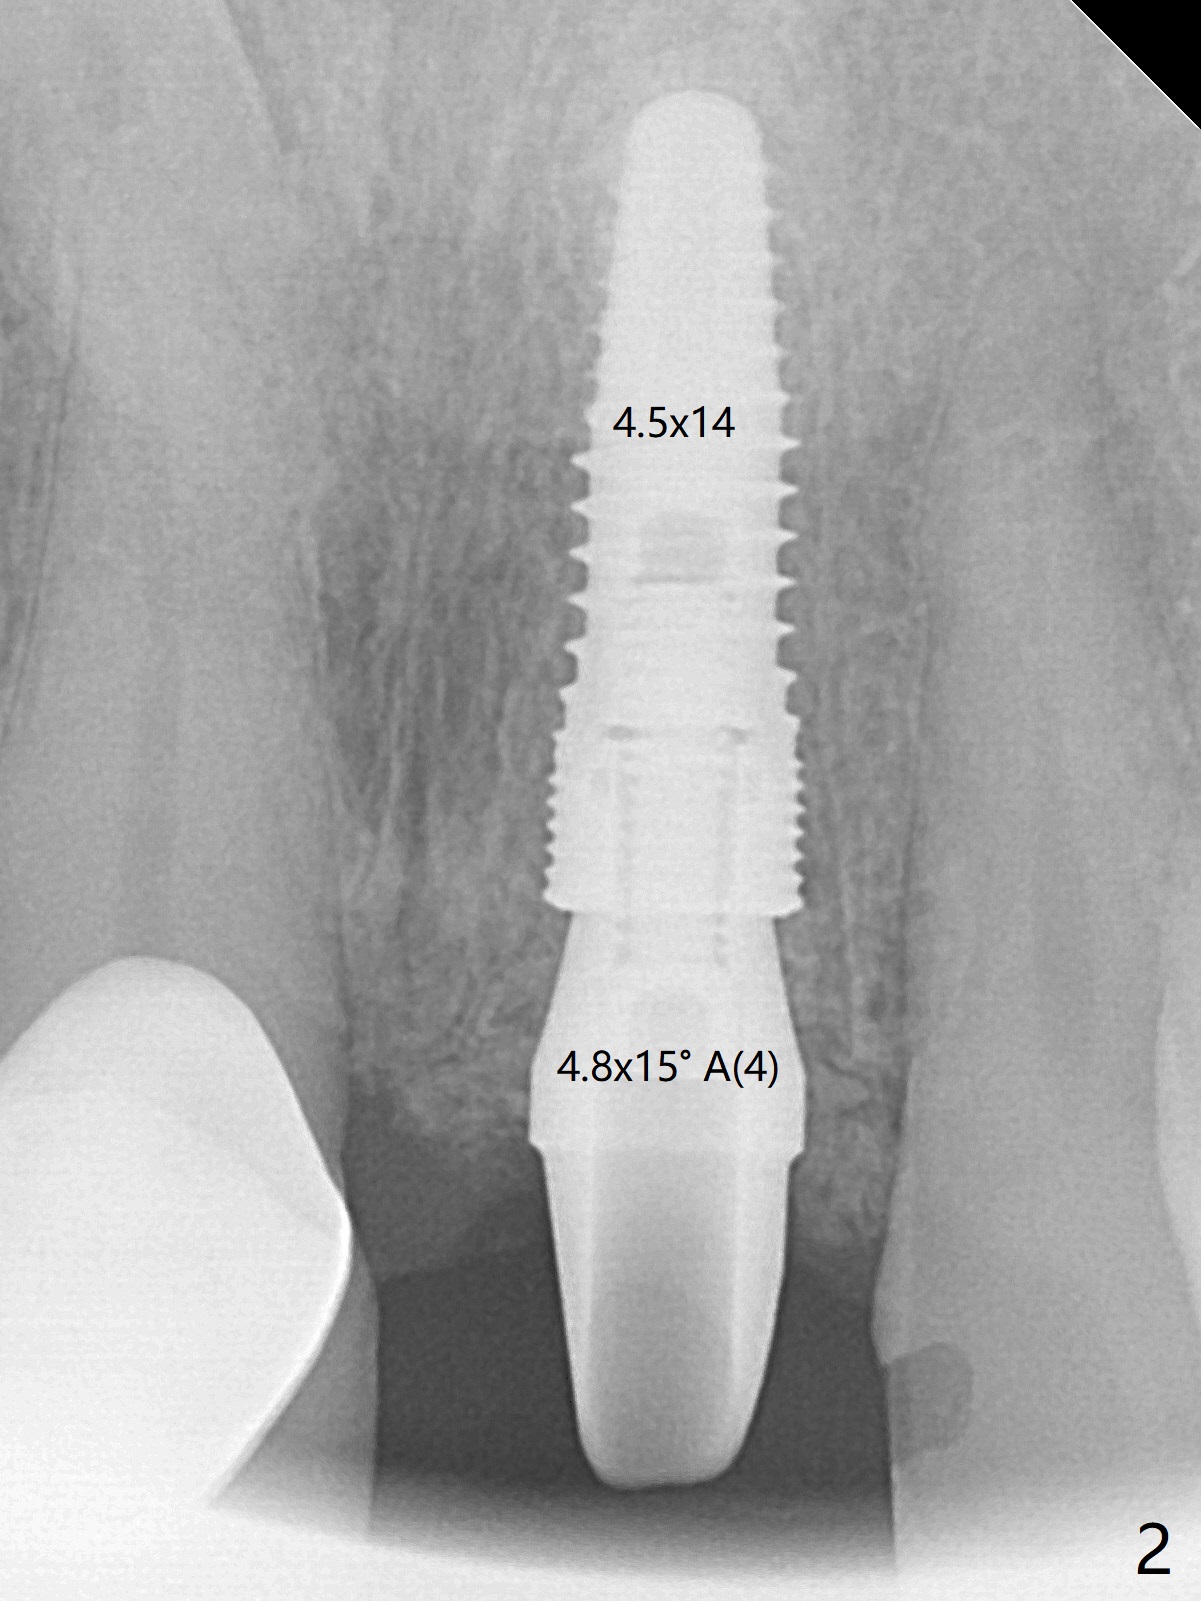

The buccal plate at #9 remains intact in spite of difficult extraction. Osteotomy is initiated in the palatal slope of the socket (Fig.1). The latter looks large when osteotomy is finished for a 3.8 mm implant. Without further osteotomy, a 4.5x14 mm SM implant is placed with primary stability (Fig.2). Without much attention, the coronal end of the bone-level implant is gradually deviated buccal, although the buccal gap is still 2 mm. An angled abutment is used (Fig.2); the future access hole is also buccal. Screw retention is impossible for cosmetic reason (Fig.3). To keep the access incisal and palatal, keep removing palatal bone sequentially. Or start osteotomy in the mid point of the palatal slope and keep the coronal end of the trajectory (Fig.5 pink line) palatal to the imagined incisal edge (Fig.4 white outline). The implant should be small (3.5 mm instead of 4.5 mm) so that it is easy to change the trajectory. The bone graft seems to have disappeared 3.5 months postop; the implant appears to have not been placed deep enough (Fig.6). In fact the implant plateau is < 2 mm subgingival palatal. An anterior immediate implant should be placed deep to reduce periimplantitis. There is reduced risk associated with abutment screw loosening, as compared to the posterior. Luckily the patient has used water pik since implant placement. On the other hand, water pik may be related to loss of bone graft. Therefore, water pik should be used 1 month post bone graft associated with immediate implant. The bone graft remains around the abutment cuff 4 months postop (Fig.7; immediately post cementation).